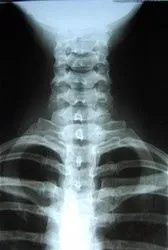

X-rays are often taken on most patients to give the doctor an inside look at what is going on with the bone structure of the entire spine and surrounding skeletal structure. From this x-ray, the doctor can tell your current spine angles as well as any further issues possibly needing additional diagnostic tests such as an MRI.